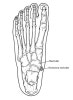

부주상골(accessory navicular bone)은 주상골 내측에 있는 부골로 주상골과 반관절을 형성하고 후경골근의 일부가 부착합니다.

분류

Type 1 : 주상골 체부와 붙어 있지 않고 잘 경계 지어져 있는, 원형 또는 타원형의 매우 작은(대개 2~3 mm) 부골입니다. 주상골과 골성이나 연골성으로 결합하지 않으며 후경골건의 족저부에 존재하여 종자골(sesamoid bone) 성격을 띱니다. 부주상골의 약 30%를 차지하며 대개 증상이 없습니다.

Type 2 : 주상골 체부의 독립된 8-12 mm 크기의 부골로, 주상골과 2mm 이내의 간격을 두고 섬유-연골성 판(fibrocartilaginous plate)으로 나뉘어 연골성 결합(synchondrosis)을 합니다.

주상골 체부와 연결되는 각에 따라 2a형과 2b형으로 소분류 하는데, 제 2a형은 2b형에 비해 작은 각으로 체부에 붙어서 견열 손상에 더 취약합니다.

3. Type 3 : 부주상골이 주상골 체부와 골성 유합으로 연결된 형태로 원뿔 모양의 주상골을 형성하는데 대부분 증상을 일으키지 않습니다.